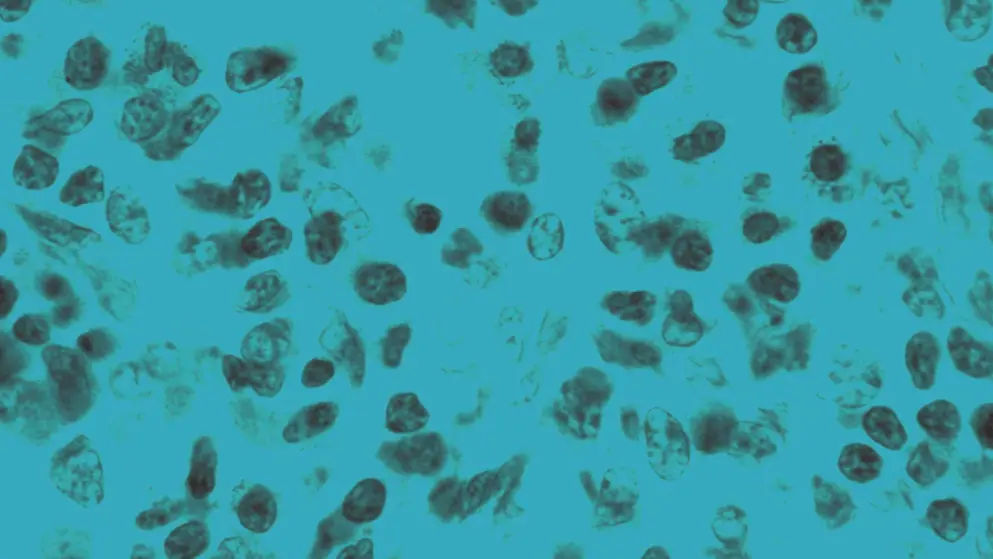

Food allergies are immune-mediated adverse reactions to specific foods. In immunoglobulin E (IgE)-mediated food allergy, the immune system mistakenly identifies a food protein as harmful and produces IgE antibodies in response.